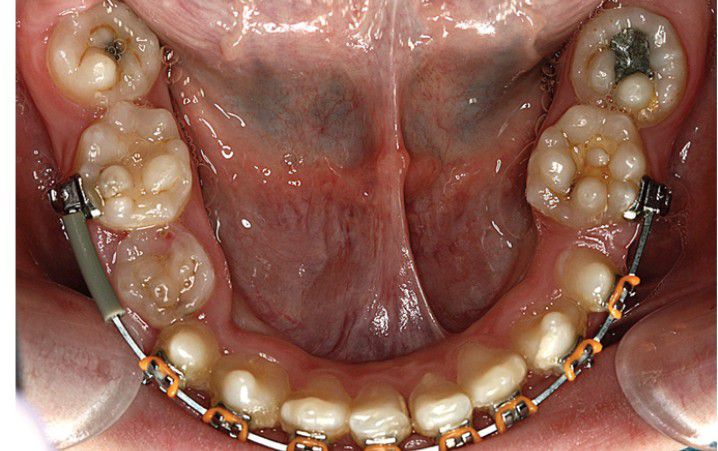

Lobodontia

Lobodontia. Mandibular molars demonstrating a multitubercular appearance